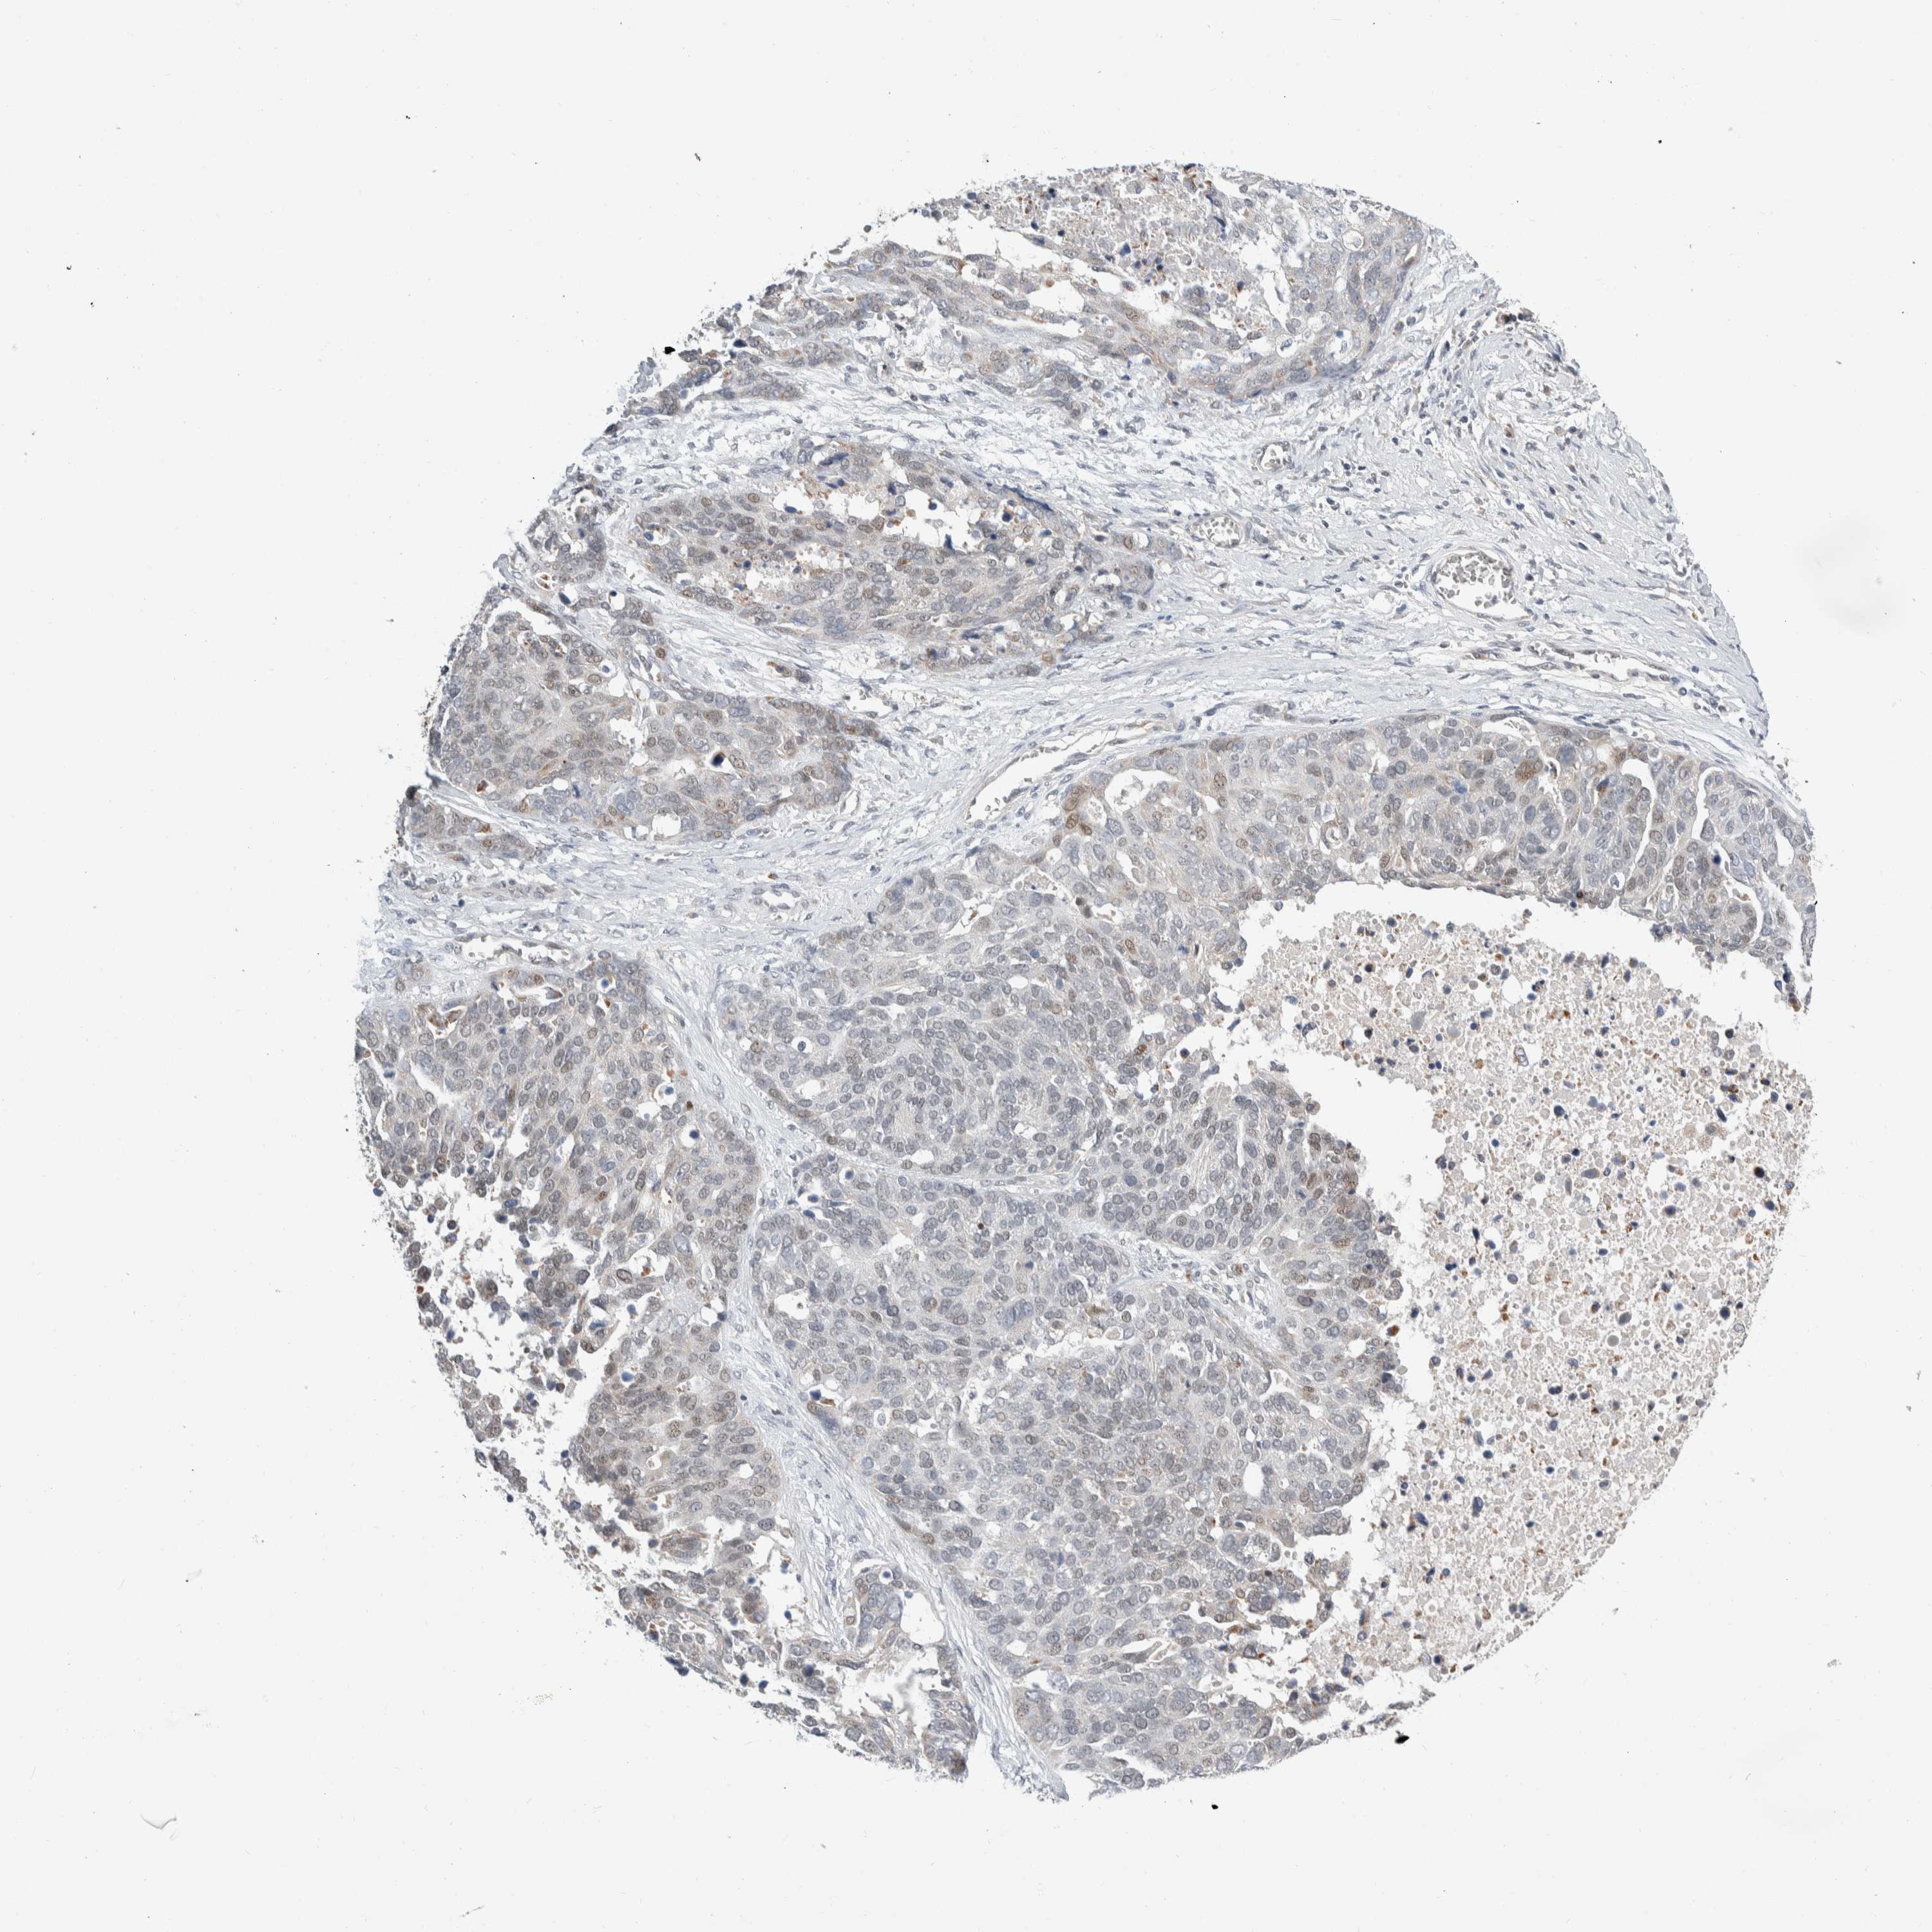

OVARIAN CANCER - Protein expressioni

A mouse-over function shows sample information and annotation data. Click on an image to view it in a full screen mode. Samples can be filtered based on level of antibody staining by selecting one or several of the following categories: high, medium, low and not detected. The assay and annotation is described here.

Note that samples used for immunohistochemistry by the Human Protein Atlas do not correspond to samples in the TCGA dataset.

Antibody stainingi

Antibody staining in the annotated cell types in the current human tissue is reported as not detected, low, medium, or high, based on conventional immunohistochemistry profiling in selected tissues. This score is based on the combination of the staining intensity and fraction of stained cells.

Each image is clickable and will lead to virtual microscopy that enables deeper exploration of all samples and also displays staining intensity scores, fraction scores and subcellular localization as well as patient and tissue information for each sample.

Antibody HPA024361

Antibody HPA064939

Cystadenocarcinoma, serous, NOS

Carcinoma, endometroid

Cystadenocarcinoma, mucinous, NOS

Carcinoma, NOS